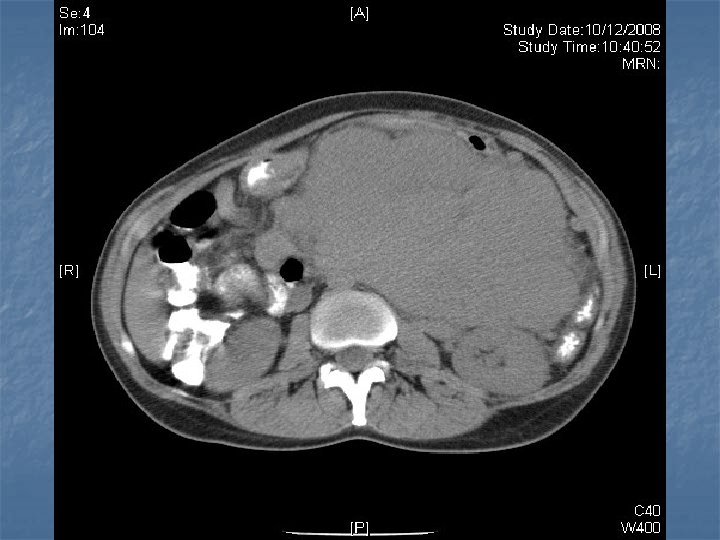

n n n PRETREATMENT INVESTIGATIONS: FBC, Renal and liver function, LDH, urate, Ig. GS. Histology review. Marrow aspirate+trephine (cytogenetics, immunology) CD 4 , HIV viral load. CT Scans. (MR Brain) (PET scan ) Echo / LVEF CMV, Hep B+C, Toxoplasma serology MAI screen. LP for CSF cytology +/- intrathecal Rx. (DLBC , Burkitt, Plasmablastic).